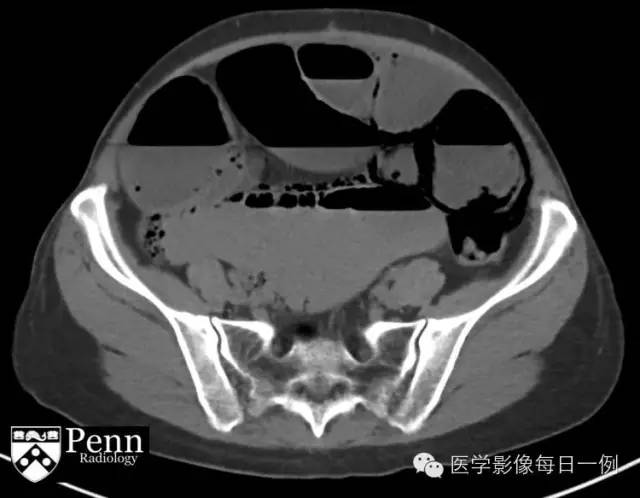

CT of abdomen/pelvis

6.可见腹膜内游离气体

7.可见肠壁积气

8.门静脉内见气体

9.肠系膜上静脉内见栓子

10.可见小肠扩张肠袢

【答案】1.A 2.B 3.B 4.A 5.A 6.A 7.A 8.A 9.B 10.A

【诊断】此影像学表现应考虑肠缺血(尽管梗阻本身可导致积气)

【临床随访】患者经保守治疗,未进行手术,梗阻缓解。